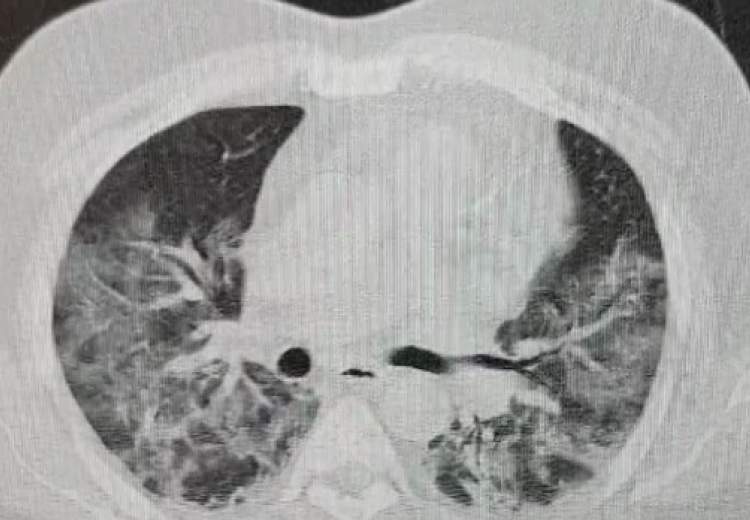

ریه فردی که به کرونا مبتلا شده چگونه است؟